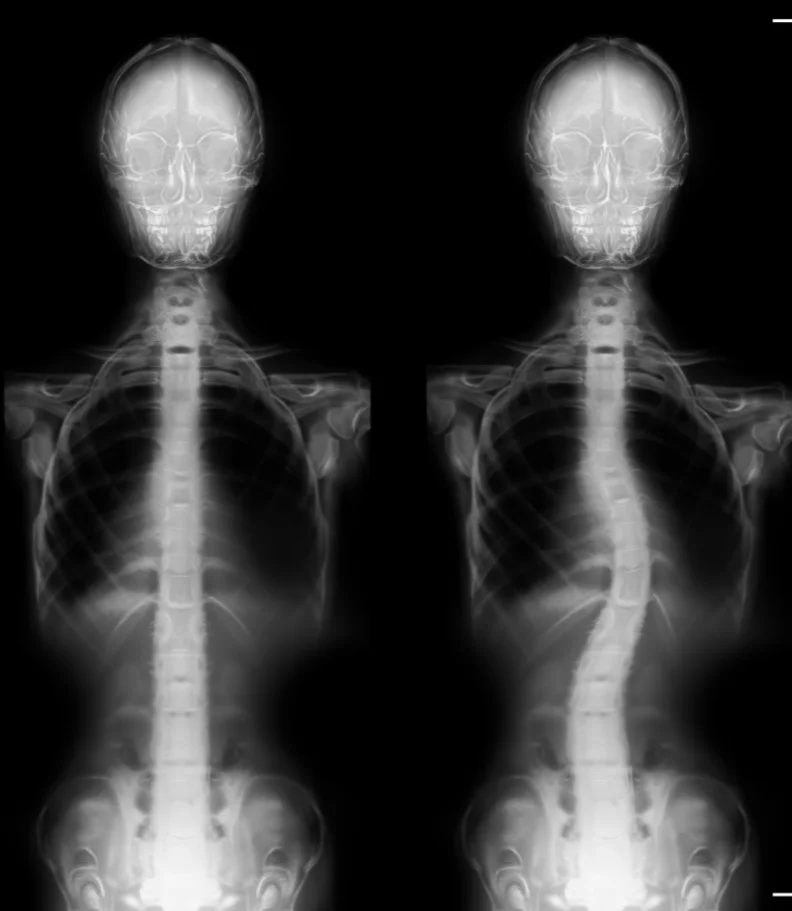

If you're experiencing scoliosis or have been told you have a curved spine in Glenside, PA, you're certainly not alone. We understand how concerning it can be to notice changes in posture or feel self-conscious about uneven shoulders, especially as these issues affect comfort during school, work, or local team practices. Our patients often share that they worry about the impact of scoliosis when participating in activities, carrying backpacks, or sitting through long community events. You might notice muscle fatigue, joint stiffness, or back pain after standing for extended periods or taking walks through Glenside. We frequently see patients who are concerned about scoliosis symptoms and are looking for answers and support. At our practice in Glenside, PA, we take a proactive and personalized approach, offering thorough assessment and encouragement for your journey. With targeted scoliosis help, including chiropractic evaluation and guided exercise plans, our team aims to support your comfort, confidence, and ability to enjoy life in Glenside without limitation.

Our scoliosis care process in Glenside, PA emphasizes thoroughness and a positive patient experience.